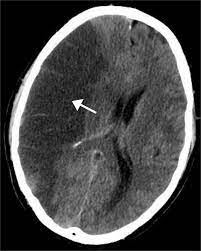

Acute Ischemic Stroke Nejm

Acute Ischemic Stroke Nejm from www.nejm.org